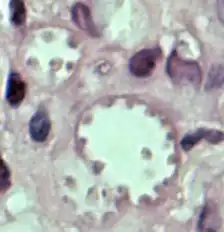

Leishmania mexicana é uma espécie de protozoário flagelado da família Trypanosomatidae. A espécie é o agente etiológico da leishmaniose cutânea do Novo Mundo.